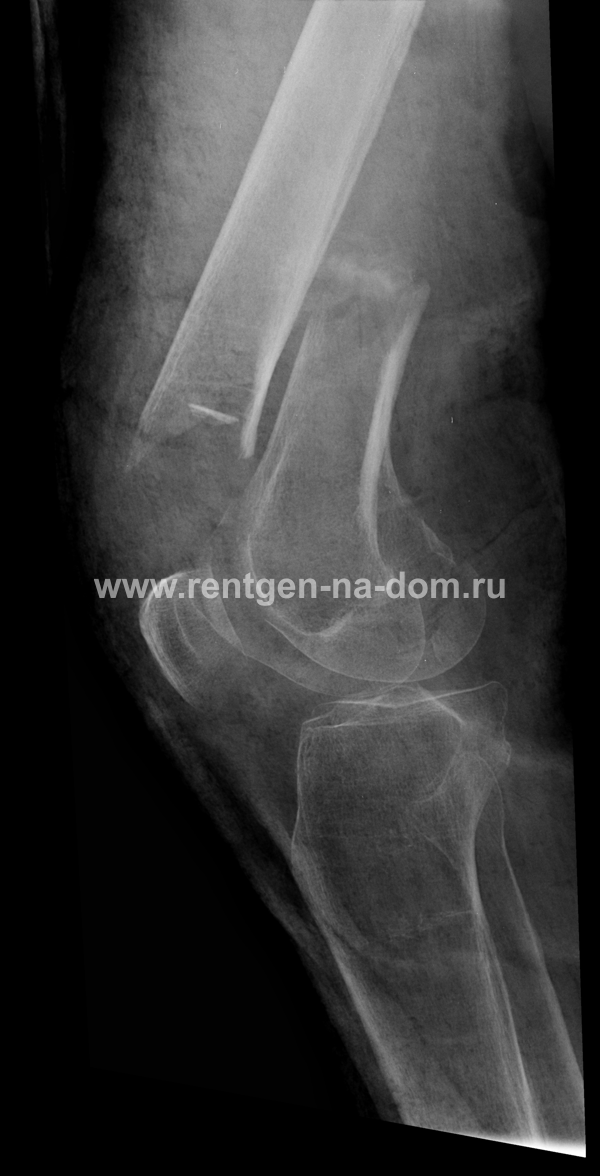

После получения травмы и остеосинтеза

Через два месяца после получения травмы и остеосинтеза аппаратом КСТ.  Ехать в больницу для контрольного обследования пострадавший не мог, так беспокоили сильные боли при движениях и слабость. Вызвали рентген на дом. Выявлено неблагоприятное течение заболевания, разрушения костей под воздействием металлоконструкции и замедленная консолидация. Рекомендована госпитализация для оперативного лечения и последующей иммобилизации в гипсе.

Перелом шейки через 2 месяца